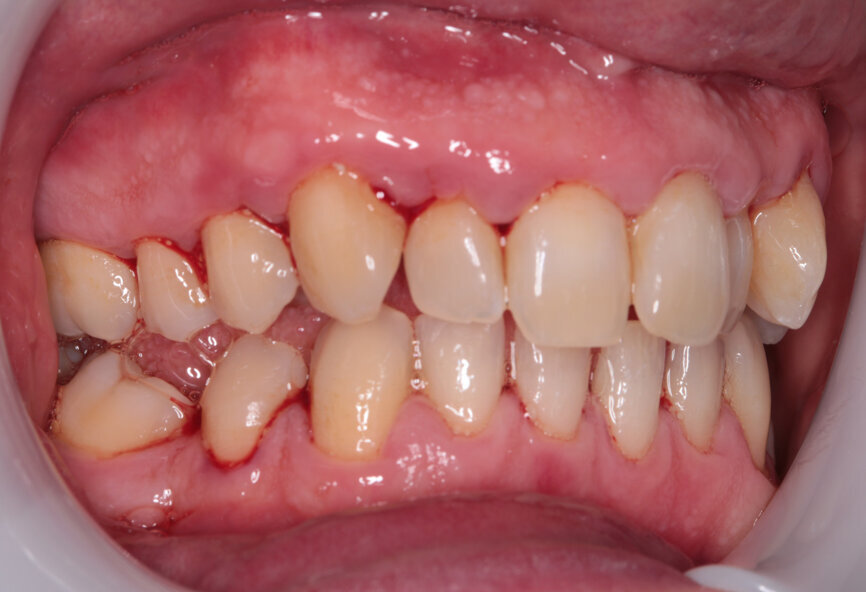

My examination revealed nothing abnormal with his extra- or intra-oral soft tissue, temporomandibular joint or range of motion. However, his oral hygiene was poor, which was not helped by the crowding of his maxillary anterior segment. In addition, tooth #48 was carious. I carried out a full orthodontic assessment (Table 1) and took photographs.

I explained that the maxillary teeth could and should be aligned, as this would likely result in easier cleaning of the teeth, plus it would improve the appearance. The patient and I agreed that the mandibular teeth could remain untouched, as this would keep the cost down, but mainly because they did not bother him. The priority was to stabilise his periodontal condition. A basic periodontal examination Code 3 and heavy bleeding were recorded in each sextant. At that visit, I performed a gross scaling using the ultrasonic scaler and used a model to demonstrate both the use of flossettes and an oscillating toothbrush.

Fig. 2: Pre treatment smile

Fig. 7: Post-scaling anterior view